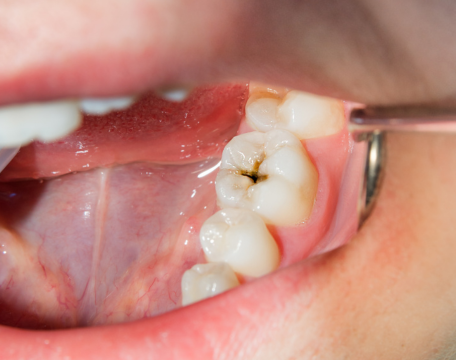

単に虫歯を治す、歯周病をケアする、歯を白くするといった部分的な治療に留まらず、なぜその症状が起きたのか、その根本原因を探ることを重視しています。

当院では虫歯や歯周病の治療はもちろん、顎関節症や咬合治療、矯正、義歯、インプラントなど多岐にわたる治療を行っております。

原因を追究し、再発リスクを抑える総合診療

咬み合わせや顎関節のバランス、日常生活の習慣など、複数の要因を探りながら最適な治療計画を立案。

短期的な痛みの除去にとどまらず、将来的にも安定した口腔環境を築くことを目指しています。